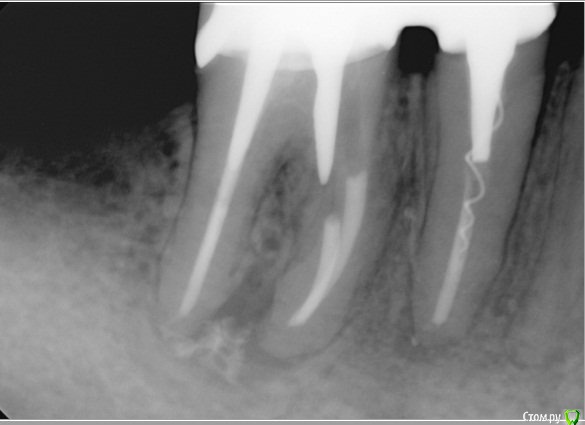

Fred Опубликовано 31 августа, 2015 Поделиться Опубликовано 31 августа, 2015 Похоже, кто-то провалился на этапе ВКВ. Что я найду под ВКВ, если конечно мне получится ее выпилить не убив зуб? http://s13.postimg.org/6n74x8f3b/Untitled_5.jpg 4 Ссылка на комментарий

Fred Опубликовано 31 августа, 2015 Автор Поделиться Опубликовано 31 августа, 2015 А в вашем случае зачем этого потерпевшего назад пригнали? Болит?Коллега заметила случайно, мост пока еще не сдан. Просит спасать ситуацию от коллеги, натворившего это. Ссылка на комментарий

Бардо Опубликовано 1 сентября, 2015 Поделиться Опубликовано 1 сентября, 2015 вторая нога в небном? На кой тогда ДБ раскурочили? Жалко зуб чего-то ( Ссылка на комментарий

Л Ю С Я Опубликовано 1 сентября, 2015 Поделиться Опубликовано 1 сентября, 2015 Мед корень похоже убит. Здесь планируется мостовидная конструкция, как я поняла, не стала бы рисковать. В крайнем случае одиночка с последующей имплантацией 2 Ссылка на комментарий